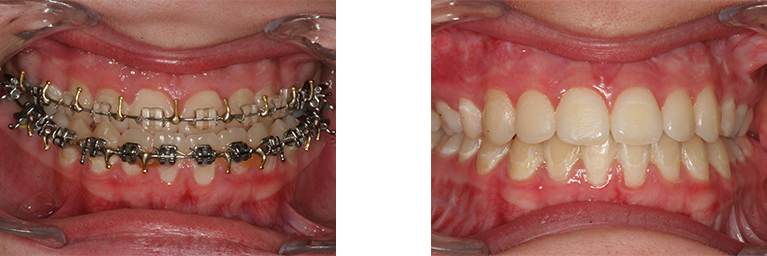

Person med skævbid og underbid